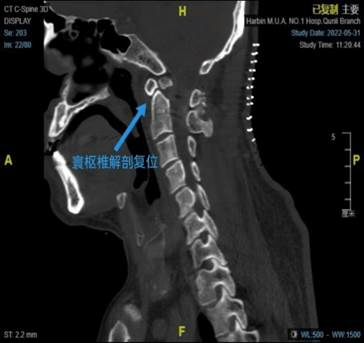

术前CT矢状位术后CT矢状位

在仔细研判张先生受伤及治疗过程,完善相关检查后赵伟教授发现,张先生在外伤后发生了寰枢椎脱位,导致脊髓受压产生四肢瘫的症状。对于确认的寰枢椎脱位,最佳的治疗方法是通过外科手术来恢复寰枢椎的正常解剖结构及稳定性。